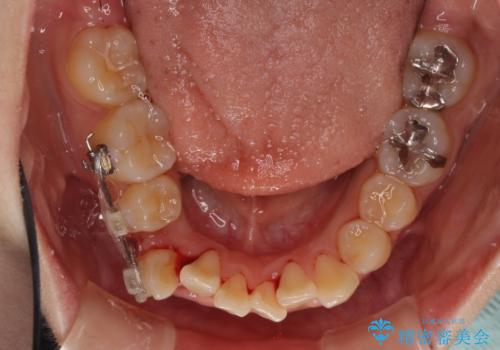

上下ともに八重歯の後ろの歯を1歯ずつ抜歯し、補助装置(リンガルアーチ)を用いて八重歯の位置を改善し、その後インビザラインにより矯正治療を行うこととしました。

途中海外留学をされたため、治療期間は長くなりましたが、事前に補助装置やワイヤー装置を併用したことで、きれいな歯列に仕上げることができました。